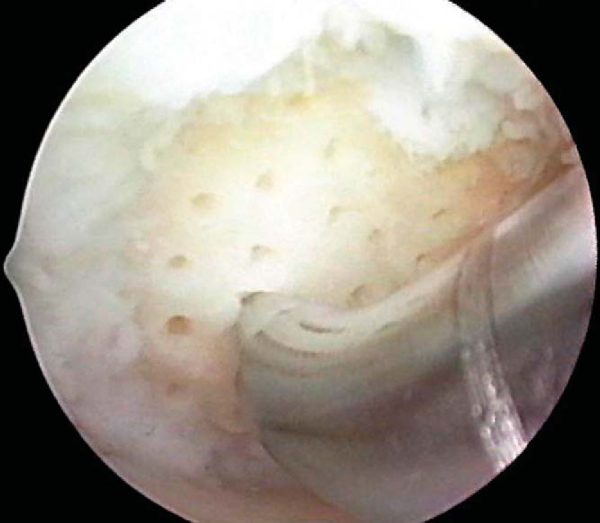

After preparation of the lesion, we use an arthroscopic awl to make multiple holes, or microfractures, in the exposed subchondral bone plate. We use an awl with an angle that permits the tip to be approximately perpendicular to the bone as it is advanced, typically 30 or 45 degrees (

Fig. 52-4

). There also is a 90-degree awl that should be used only on the patella or other soft bone. The 90-degree awl should be advanced only manually, not with a mallet. The holes are made as close together as possible, but not so close that one breaks into another, thus damaging the subchondral plate between them and potentially altering the joint shape. This technique usually results in microfracture holes that are approximately 3 to 4 mm apart. When fat droplets can be seen coming from the marrow cavity, the appropriate depth (approximately 2 to 4 mm) has been reached (

Fig. 52-5

). The arthroscopic awls produce essentially no thermal necrosis of the bone compared with hand-driven or motorized drills. We make microfracture holes around the periphery of the defect first, immediately adjacent to the healthy stable cartilage rim (see Figs. 52-4 and 52-5 [4] [5]); then we complete the process by making the microfracture holes toward the center of the defect (

Fig. 52-6

). We assess the treated lesion at the conclusion of the microfracture to ensure that a sufficient number of holes has been made before reducing the arthroscopic irrigation fluid flow (

Fig. 52-7

). After the arthroscopic irrigation fluid pump pressure is reduced, under direct visualization we are able to observe the flow of marrow fat droplets and blood from the microfracture holes into the prepared lesion (